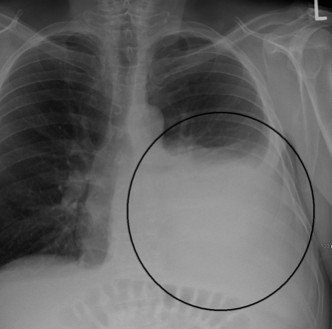

Definition

Hemothorax is a collection of blood in the space between the chest wall and the lung (the pleural cavity).